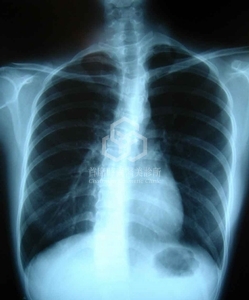

脊柱側彎造成軀幹的旋轉效應(trunk rotation), 胸脊柱右曲者較多, 左側胸部較突起+乳房也較大, 左臀也較突出.